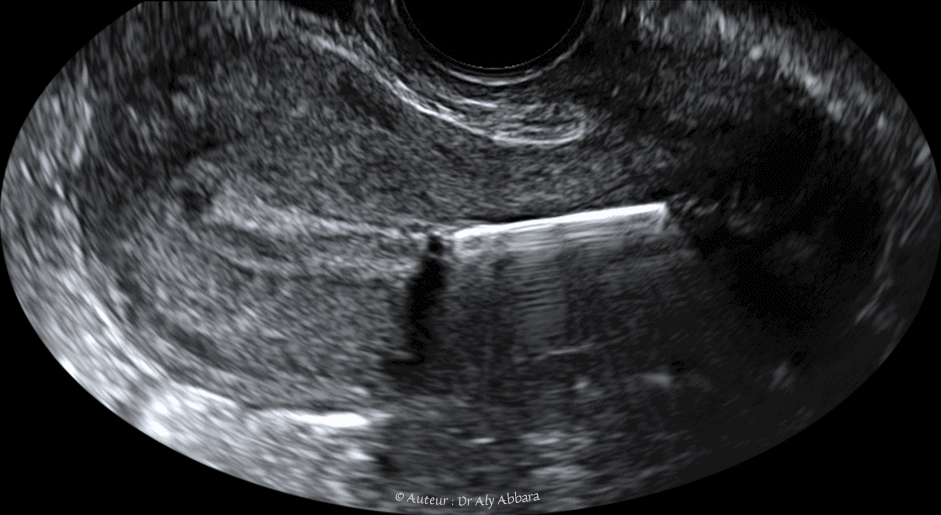

• Images échographiques montrant, sur une coupe sagittale médiane et sur une coupe coronale (frontale), un utérus normal avec le phénomène particulier de rejet de DIU en le déplaçant vers le canal endocervical.

• Le fait que ce DIU possède des crochets latéraux explique pourquoi, une fois que l'utérus l'a expulsé de sa cavité corporéale, il reste souvent accroché aux parois latérales du canal endocervical (comme le montre la 2ème image de cet article).